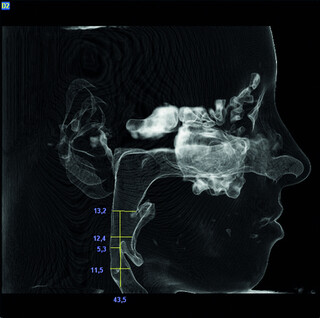

- Digitale Vermessung der oberen Luftwege

Obstruktives Schlafapnoe-Syndrom (OSAS)

Schlafbezogene Atemstörungen können ernste Gesundheitsfolgen verursachen und werden oft erst spät erkannt.

Bei im Schlaf erschlafftem Zungengrund kann im Krankheitsfall nicht mehr genügend Luft den Rachenraum durchströmen, was oft auch zum Schnarchen führt. Der Körper wird nicht ausreichend mit Sauerstoff versorgt. Typischerweise klagen betroffene Patienten über Tagesmüdigkeit und Leistungsminderung. Unbehandelt führt das OSAS oft zu chronischen Erkrankungen wie Bluthochdruck und Herzerkrankungen.

Ursächlich für ein OSAS kann z.B. auch ein zurückliegender Unterkiefer sein, welcher anatomisch den Zungengrund nach hinten drängt.

Mittels Zahnschiene (Protrusionsschiene) besteht die Möglichkeit, einen positiven Effekt der Unterkiefervorverlagerung zu testen und ggf. das Ausmaß der notwendigen Verlagerung festzustellen.

Durch eine Umstellungsosteotomie mit Kiefervorverlagerung (oft Ober- und Unterkiefer gemeinsam) kann das Krankheitsbild dann ursächlich behandelt werden.